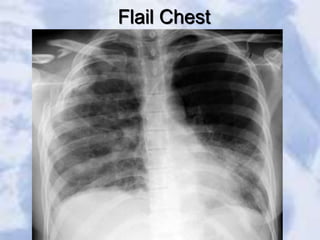

Flail Chest